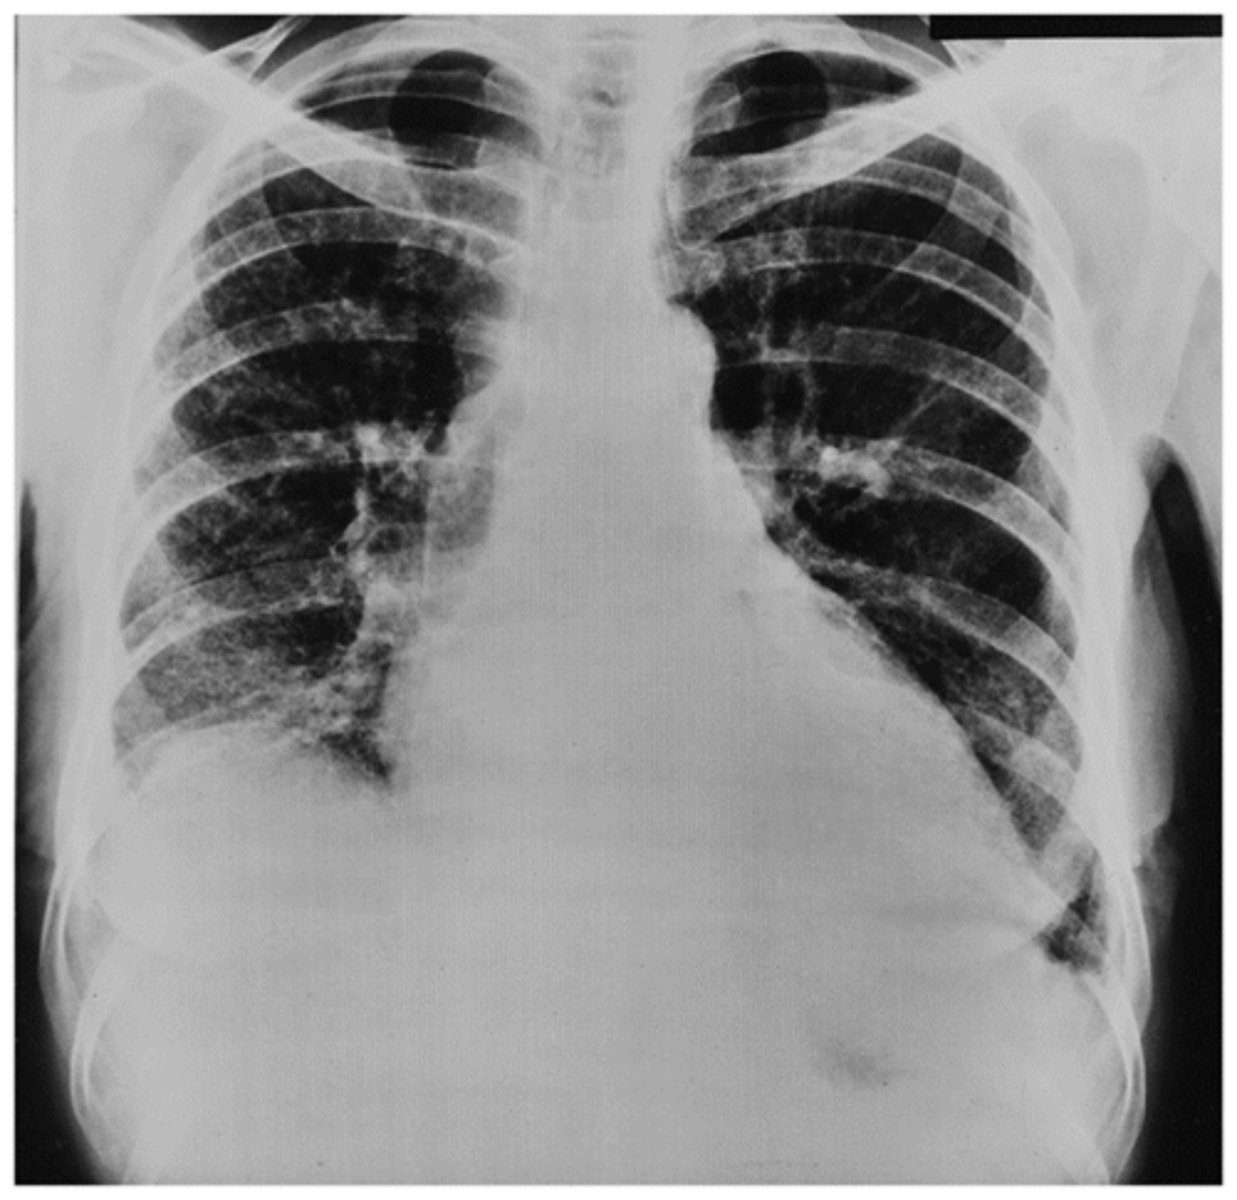

Possible CHF (presence of Kerley B lines)

What does the chest film show?

CHF (Kerley B lines- short, horizontal white lines that indicate fluid accumulation)

Interpretation?